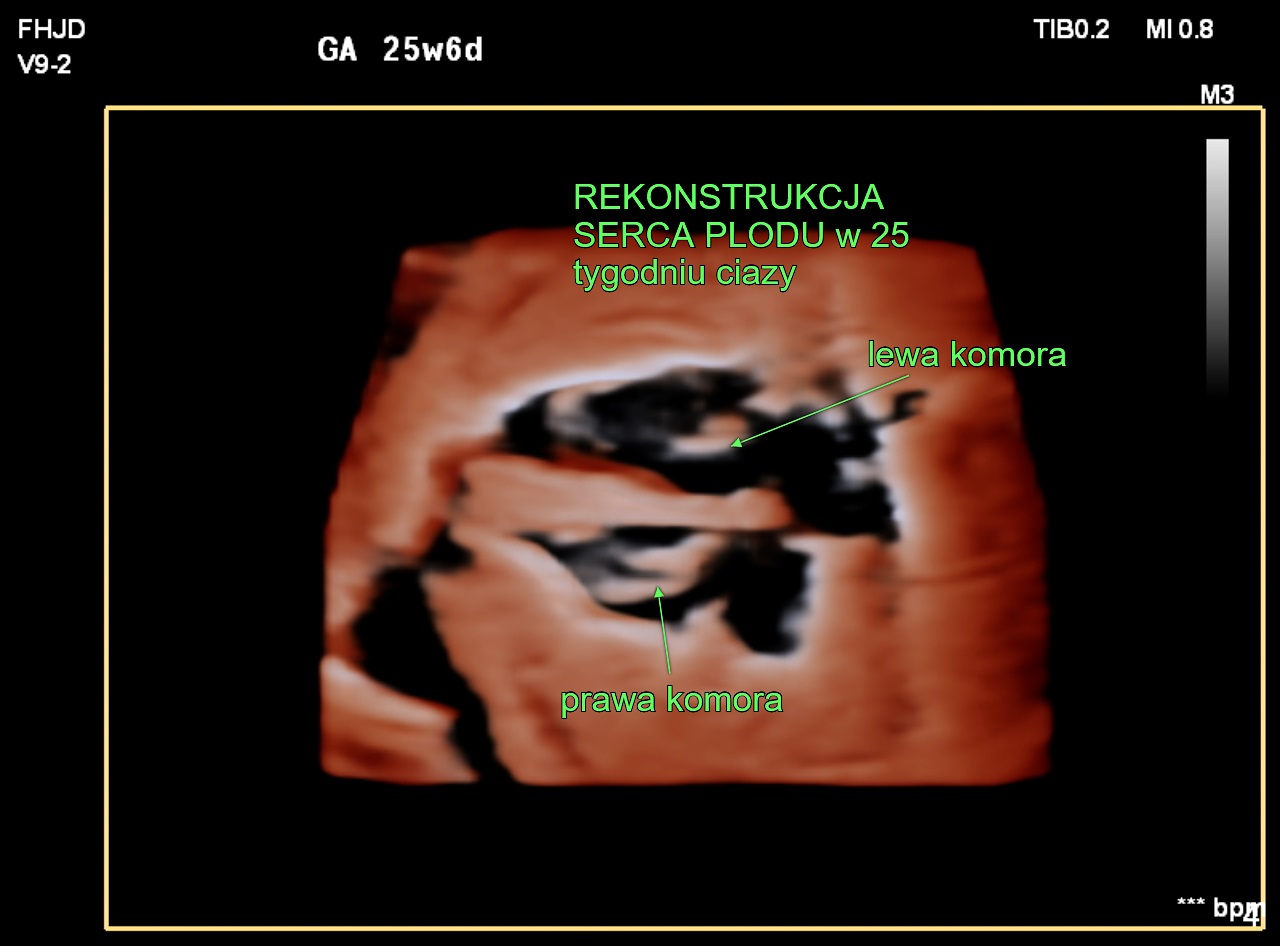

W 2011 r. kardiolodzy zajmujący się diagnostyką prenatalną w zespole prof. Joanny Szymkiewicz-Dangel oraz położnicy ze Szpitala Bielańskiego rozpoczęli pionierski w Polsce program interwencyjnej prenatalnej terapii kardiologicznej. Do zabiegów wewnątrzmacicznych kwalifikowane są płody z krytycznym zwężeniem zastawki aortalnej lub płucnej, które w innym przypadku mogłyby umrzeć lub wyniki leczenia po urodzeniu byłyby zdecydowanie gorsze.

Celem tych zabiegów jest uratowanie niedorozwiniętej lub uszkodzonej lewej lub prawej komory serca. Są to najciężej chore dzieci, którym udaje się pomóc. Zabieg poszerzenia zastawki aortalnej lub płucnej nie leczy całkowicie zastawek, ale zmniejsza nasilenie choroby i pozwala na bardziej skuteczne leczenie po urodzeniu. To dopiero pierwszy etap trudnego i długotrwałego leczenia po urodzeniu.